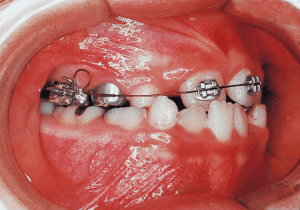

8 Beginning of 1st Phase 8-22-’88 7 years 1 month

The Edgewise appliance was applied locally (8) and removed after 11 months (9). However, as the maxillary molar region gradually became crossbite, the maxillary arch was laterally expanded using a quad helix.